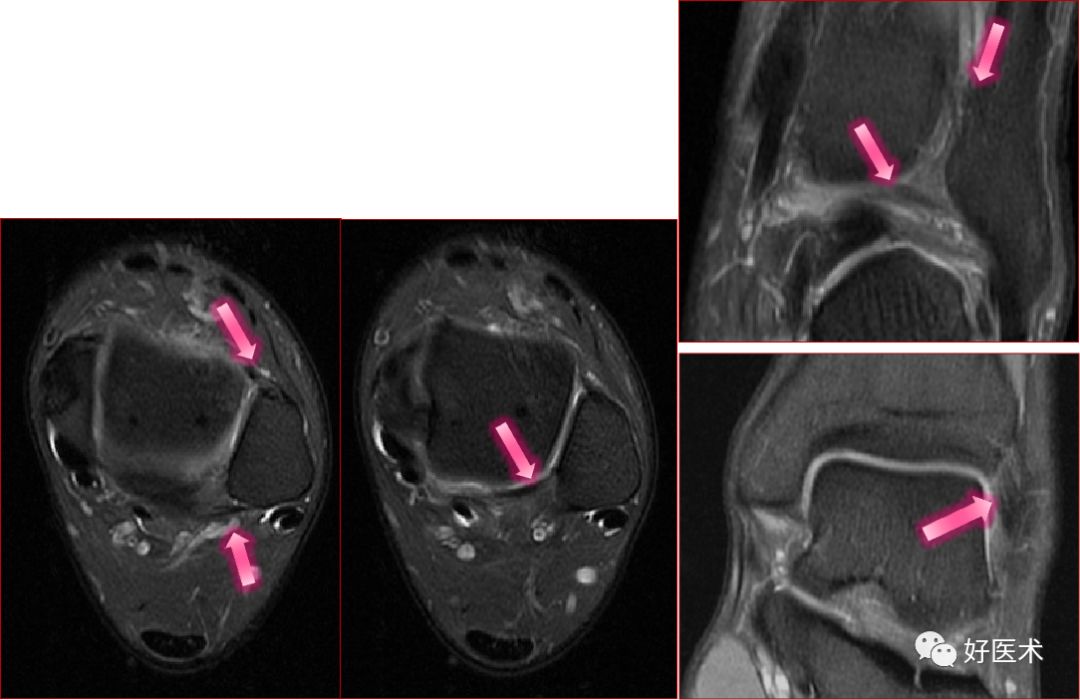

三角韧带

踝关节内侧韧带又称三角韧带,为强劲的三角形纤维束。上方附着于内踝尖及其前后缘;浅层纤维为胫舟部,前行附着于舟骨粗隆,部分与跟舟足底韧带的内侧面融合;中间部为胫跟部,下方附着于载距突;后部为胫距后部,纤维附着于至距骨内侧面和内侧结节。

三角韧带撕裂